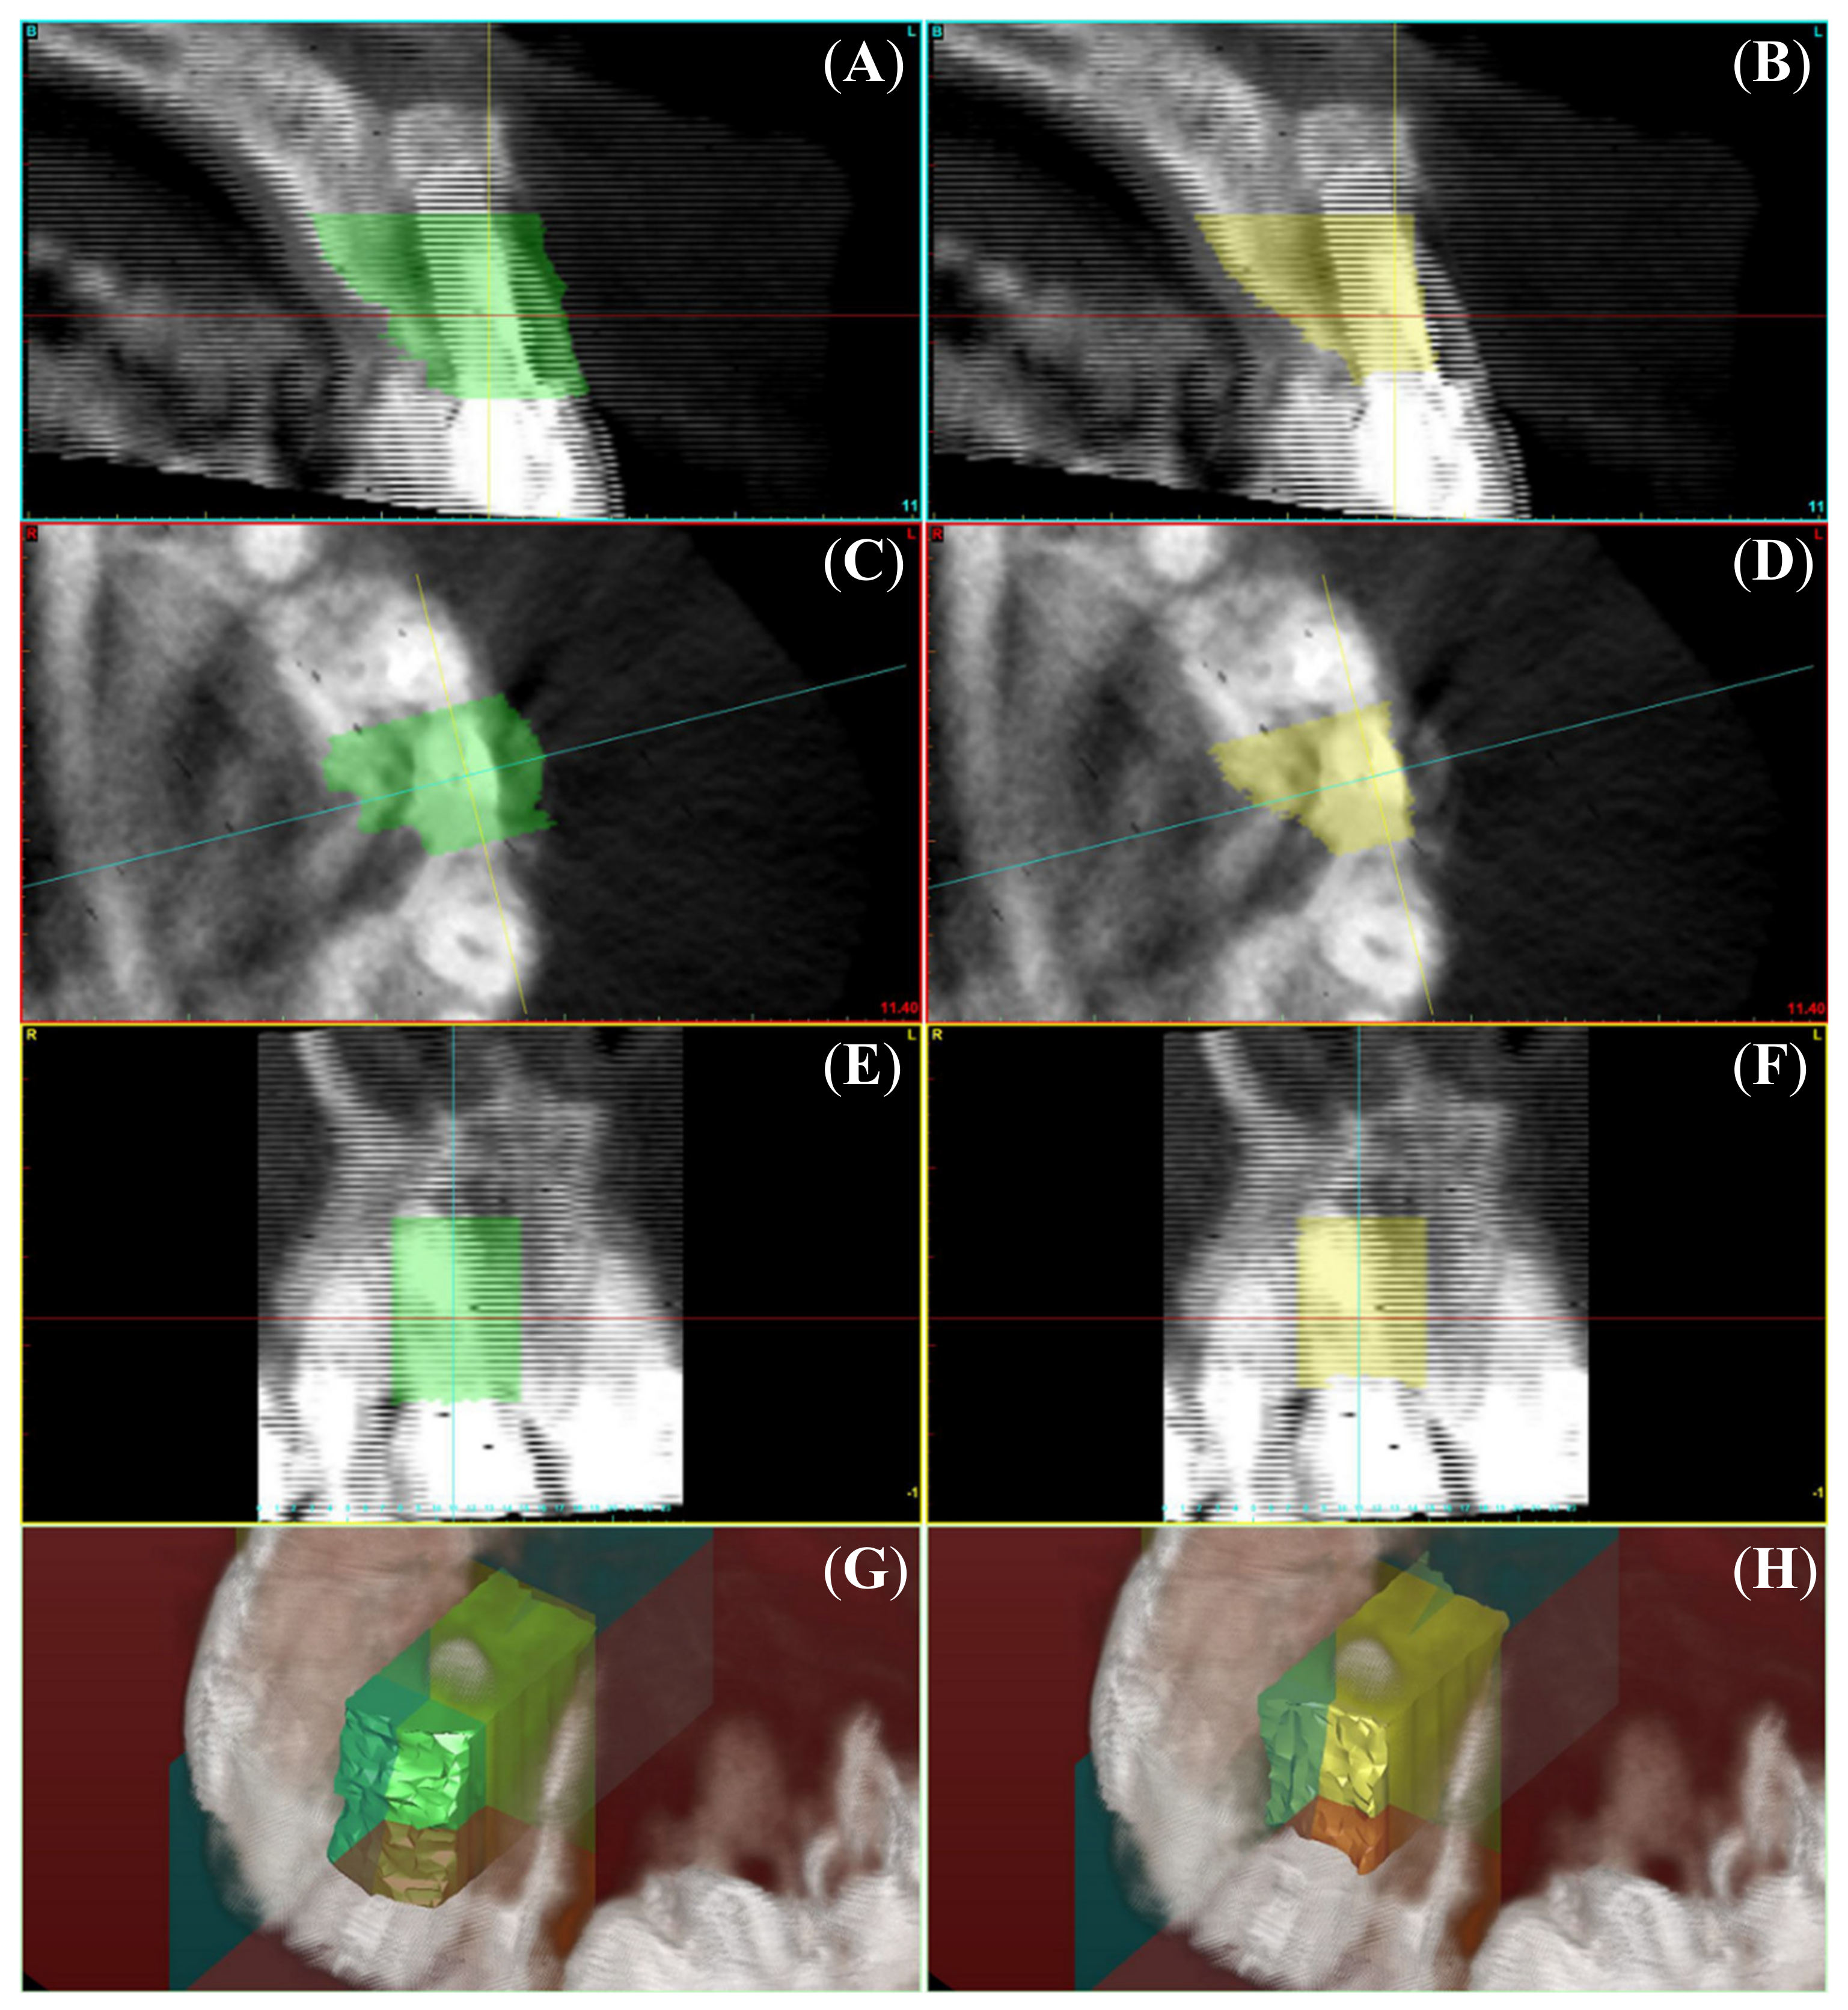

Appendix A